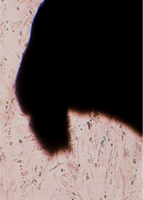

Монослой оставался целостностным и равномерным на всей поверхности чашки Петри, клетки вблизи образца сохраняли характерное для культуры фибробластов взаимное расположение и направление роста (рис. 39).

Морфология их также соответствовала сроку роста: клетки веретеновидной формы с гомогенной цитоплазмой и центрально расположенным пузырьковидным ядром неплотно прилежали друг к другу и анастомозировали своими отростками.

В последующие сроки мы также не наблюдали каких-либо морфологических признаков воздействия имплантата на культуру фибробластов.

Клетки формировали равномерный монослой, плотность которого соответствовала сроку роста культуры после пассирования и не зависела от расстояния до образца (таб. 17).